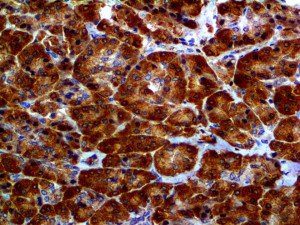

The first cytokines released are interleukin 1β (IL-1β) and tumor necrosis factor-α (TNF-α), which attract a variety of circulating white blood cells (WBCs) to the infection site, including neutrophils, monocytes, macrophages, and natural killer (NK) cells. This response, along with the antipathogenic chemicals released by these cells (i.e., complement), comprise the innate immune response. These cells directly attack the invading pathogen and also release additional cytokines, chief among them interleukin-1 and 6 (IL-6). IL-6 is essential for invoking the adaptive immune response, which calls T-cells, B-cells, and T helper (Th) cells to the infection site. IL-6 also stimulates further recruitment, proliferation and activation of macrophages.

It is the ICU physician who is most likely to witness one of the deadliest manifestations of the abnormal immunological response, the cytokine storm syndrome (CSS). This response is also referred to by some as the cytokine release syndrome (CRS). CSS is characterized by continuous activation and expansion of macrophage and lymphocyte populations, which secrete large amounts of cytokines, causing the cytokine storm. This massive cytokine release is akin to hemophagocytic lymphohistiocytosis (HLH) disease, a syndrome characterized by initial unchecked and persistent activation of cytotoxic T lymphocytes and NK cells.

This activation induces inflammatory monocytes to highly express IL-6, starting a localized and then systemic cascade effect that results in hyperproduction of IL-6, which accelerates the inflammatory process. Because IL-6 also increases vascular permeability, excessive levels cause blood vessels to become very leaky. This, along with clotting factors released from vascular endothelial cells, stimulates the coagulation cascade, resulting in microthrombosis (tiny clots), which leads to ischemia and tissue death of the kidney, intestines, heart, liver, brain and extremities.